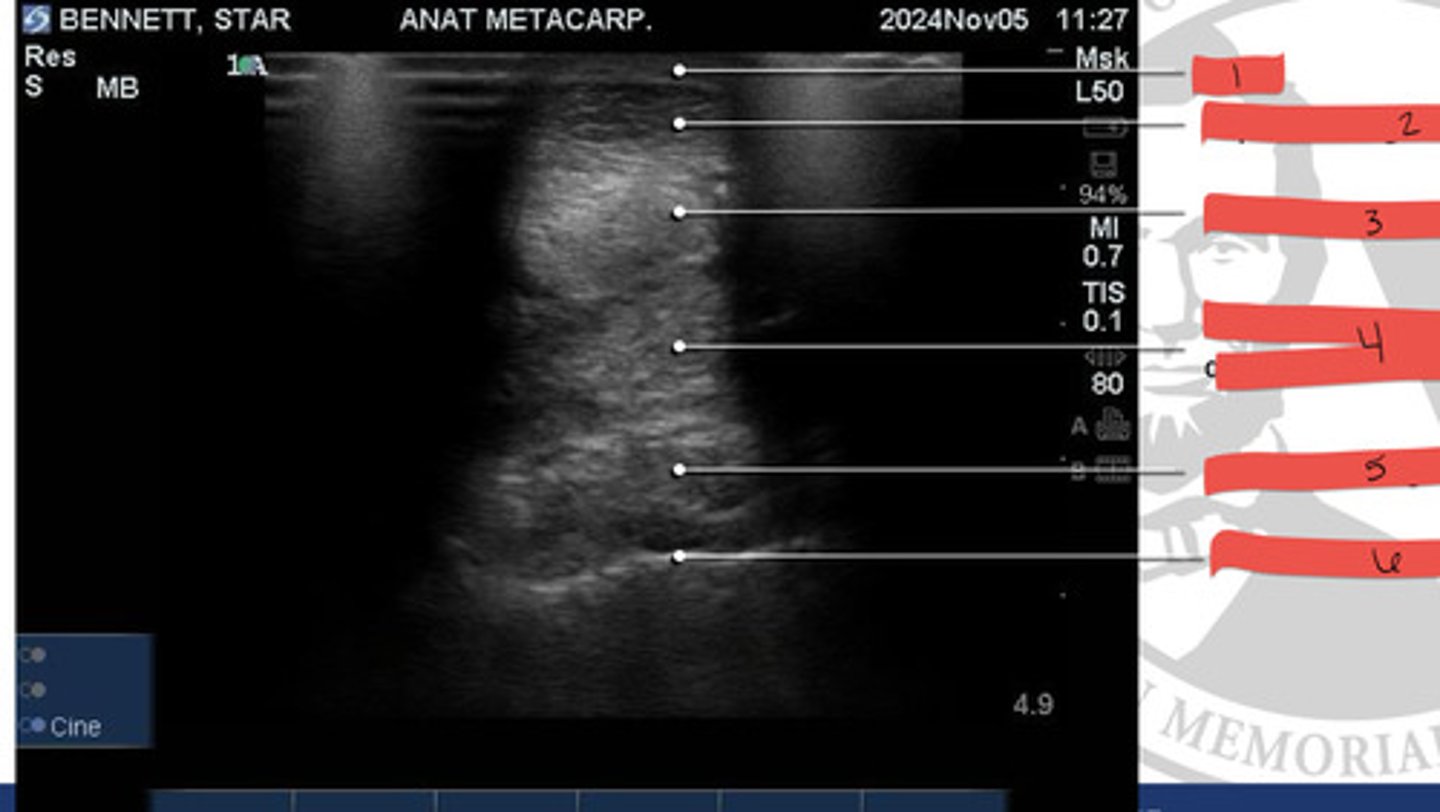

Skin

What is 1?

SDF tendon

What is 2?

DDF tendon

What is 3?

distal accessory ligament of the deep digital flexor

What is 4?

Interosseous ligament

What is 5?

Metacarpal bone III

What is 6?